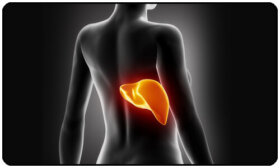

간은 몸에서 가장 크고 필수적인 장기이다. 간에서 하는 일들에는 다음과 같은 것들이 포함된다. 단백질 생성 포도당, 철분, 콜레스테롤의 대사 체내…

우리는 많은 질병이 간과 직간접적으로 관련되어 있다는 얘기를 종종 듣는다. 왜 그런 것일까? 영양분을 제대로 섭취하지 않거나 환경 오염, 스트레스, 부정적인 감정 등으로 인한 희생양으로 간이 손상되기 때문이다. 이 글에서는 간이 지쳤다는 신호와 나타나는 증상을 설명하려고 한다.